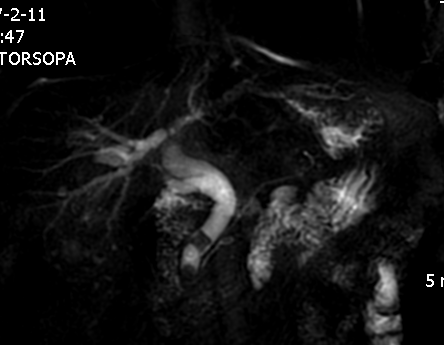

MRCP和MRU可无创性了解胆管和输尿管梗阻或狭窄的程度和病变性质。高分辨MRI对盆腔病变的诊断和鉴别诊断提供更多的诊断价值和依据。

MRCP示胆总管结石并以上系扩张